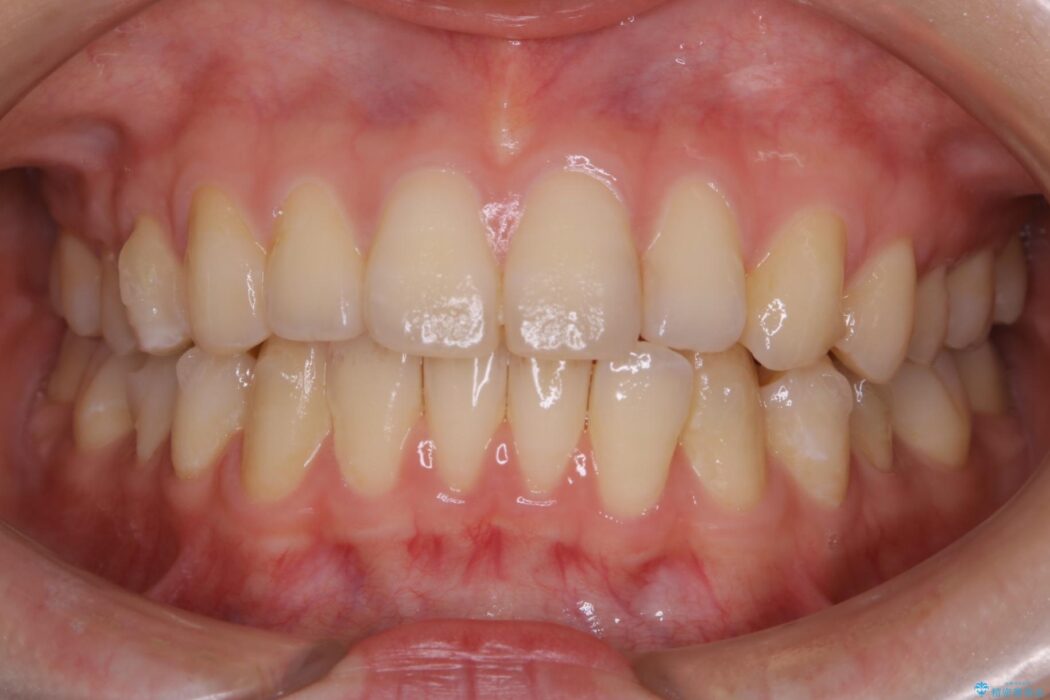

検査をしたところ奥歯の噛み合わせなどに問題が見られなかったため、軽度のねじれがある下顎前歯に焦点を当てた部分矯正の適応が可能と判断し、インビザラインのライトパッケージをご提案しました。

本症例では奥歯に関して問題がほぼ見られなかったため、部分矯正を行うことが可能と判断しました。

通常の全体矯正と比べピンポイントの部分矯正となると、動かす歯が少なくなるため治療期間が格段に短くなり、費用が抑えられることがメリットとして挙げられます。